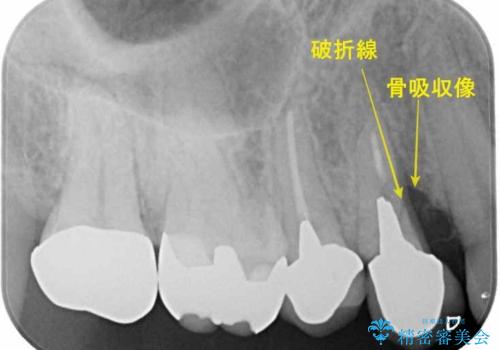

被せ物がコア(土台)ごと取れておりかつ根っこも折れてしまっている(歯根破折)状態でした。

歯根破折により保存は不可と診断し抜歯後、骨ができるのを待ってインプラントで治療を行いました。

メタルコアは度々歯根破折の原因になります。なので現在はファイバーコアが主流となっています。